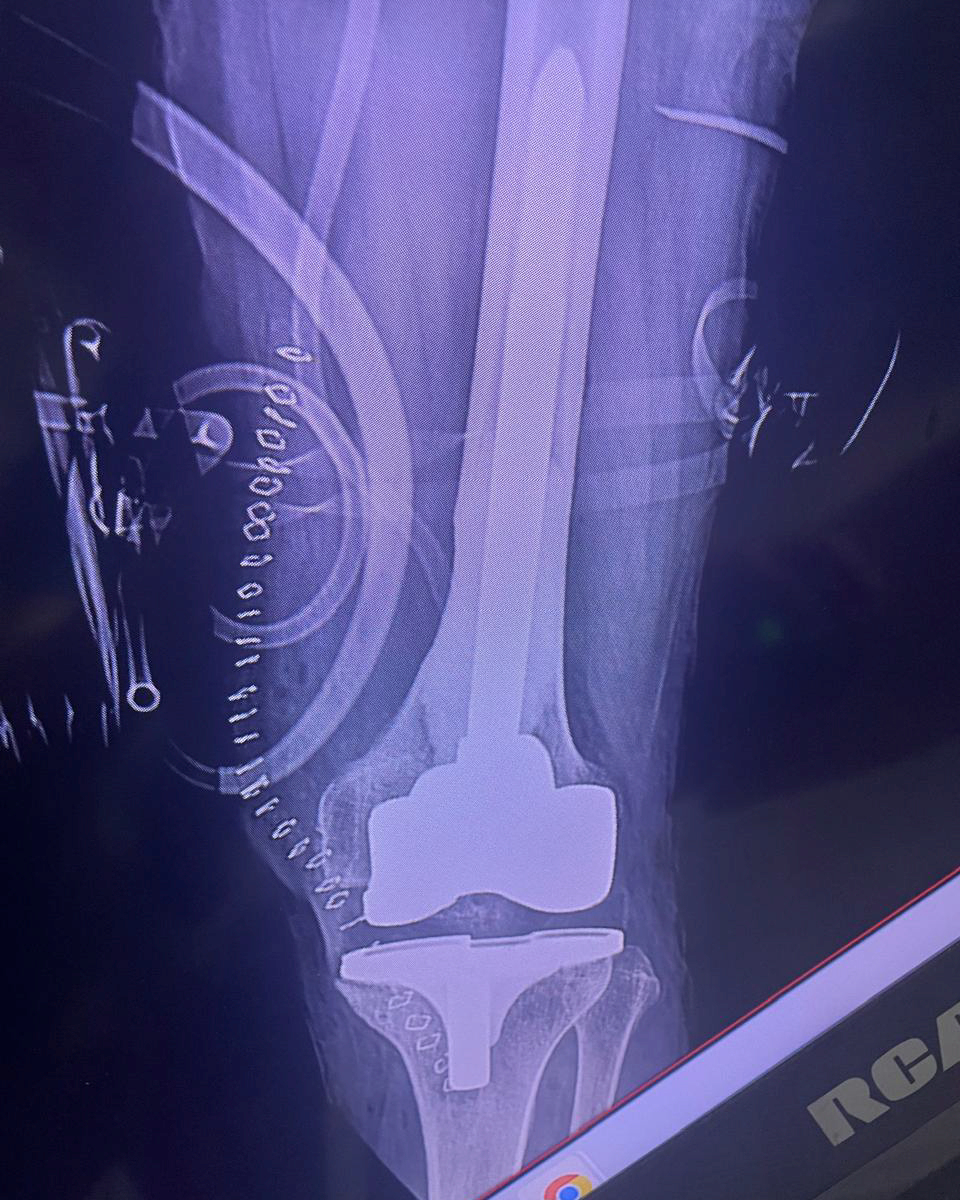

El Dr. Omar Gerardo Juárez Solano es médico especialista en Ortopedia y Traumatología de Alta Complejidad, con más de 15 años de experiencia en el diagnóstico y tratamiento quirúrgico de patología musculoesquelética — de cualquier nivel de complejidad — en pacientes de todas las edades.

Su formación de alta especialidad en el Hospital Magdalena de las Salinas (Ciudad de México), institución de referencia nacional y la de mayor volumen ortopédico en América Latina, junto con el respaldo académico de la UNAM, lo posicionan como uno de los pocos especialistas en el país con entrenamiento específico en cirugía ortopédica de alta especialidad.

Hoy, con consulta en León, Guanajuato, el Dr. Juárez Solano es el único especialista con esta formación en el Bajío, lo que significa que los pacientes de la región ya no tienen que viajar para acceder a cirugía de rescate de extremidades, resección de patología ósea compleja o cirugía reconstructiva con prótesis especializada de alta complejidad.

Procedimientos quirúrgicos especializados para tratar patología musculoesquelética con tecnología avanzada y técnicas validadas internacionalmente.

Cirugía Segura

Procedimientos quirúrgicos con tecnología avanzada y cuidado humano. Trabajamos con equipos multidisciplinarios para minimizar riesgos.